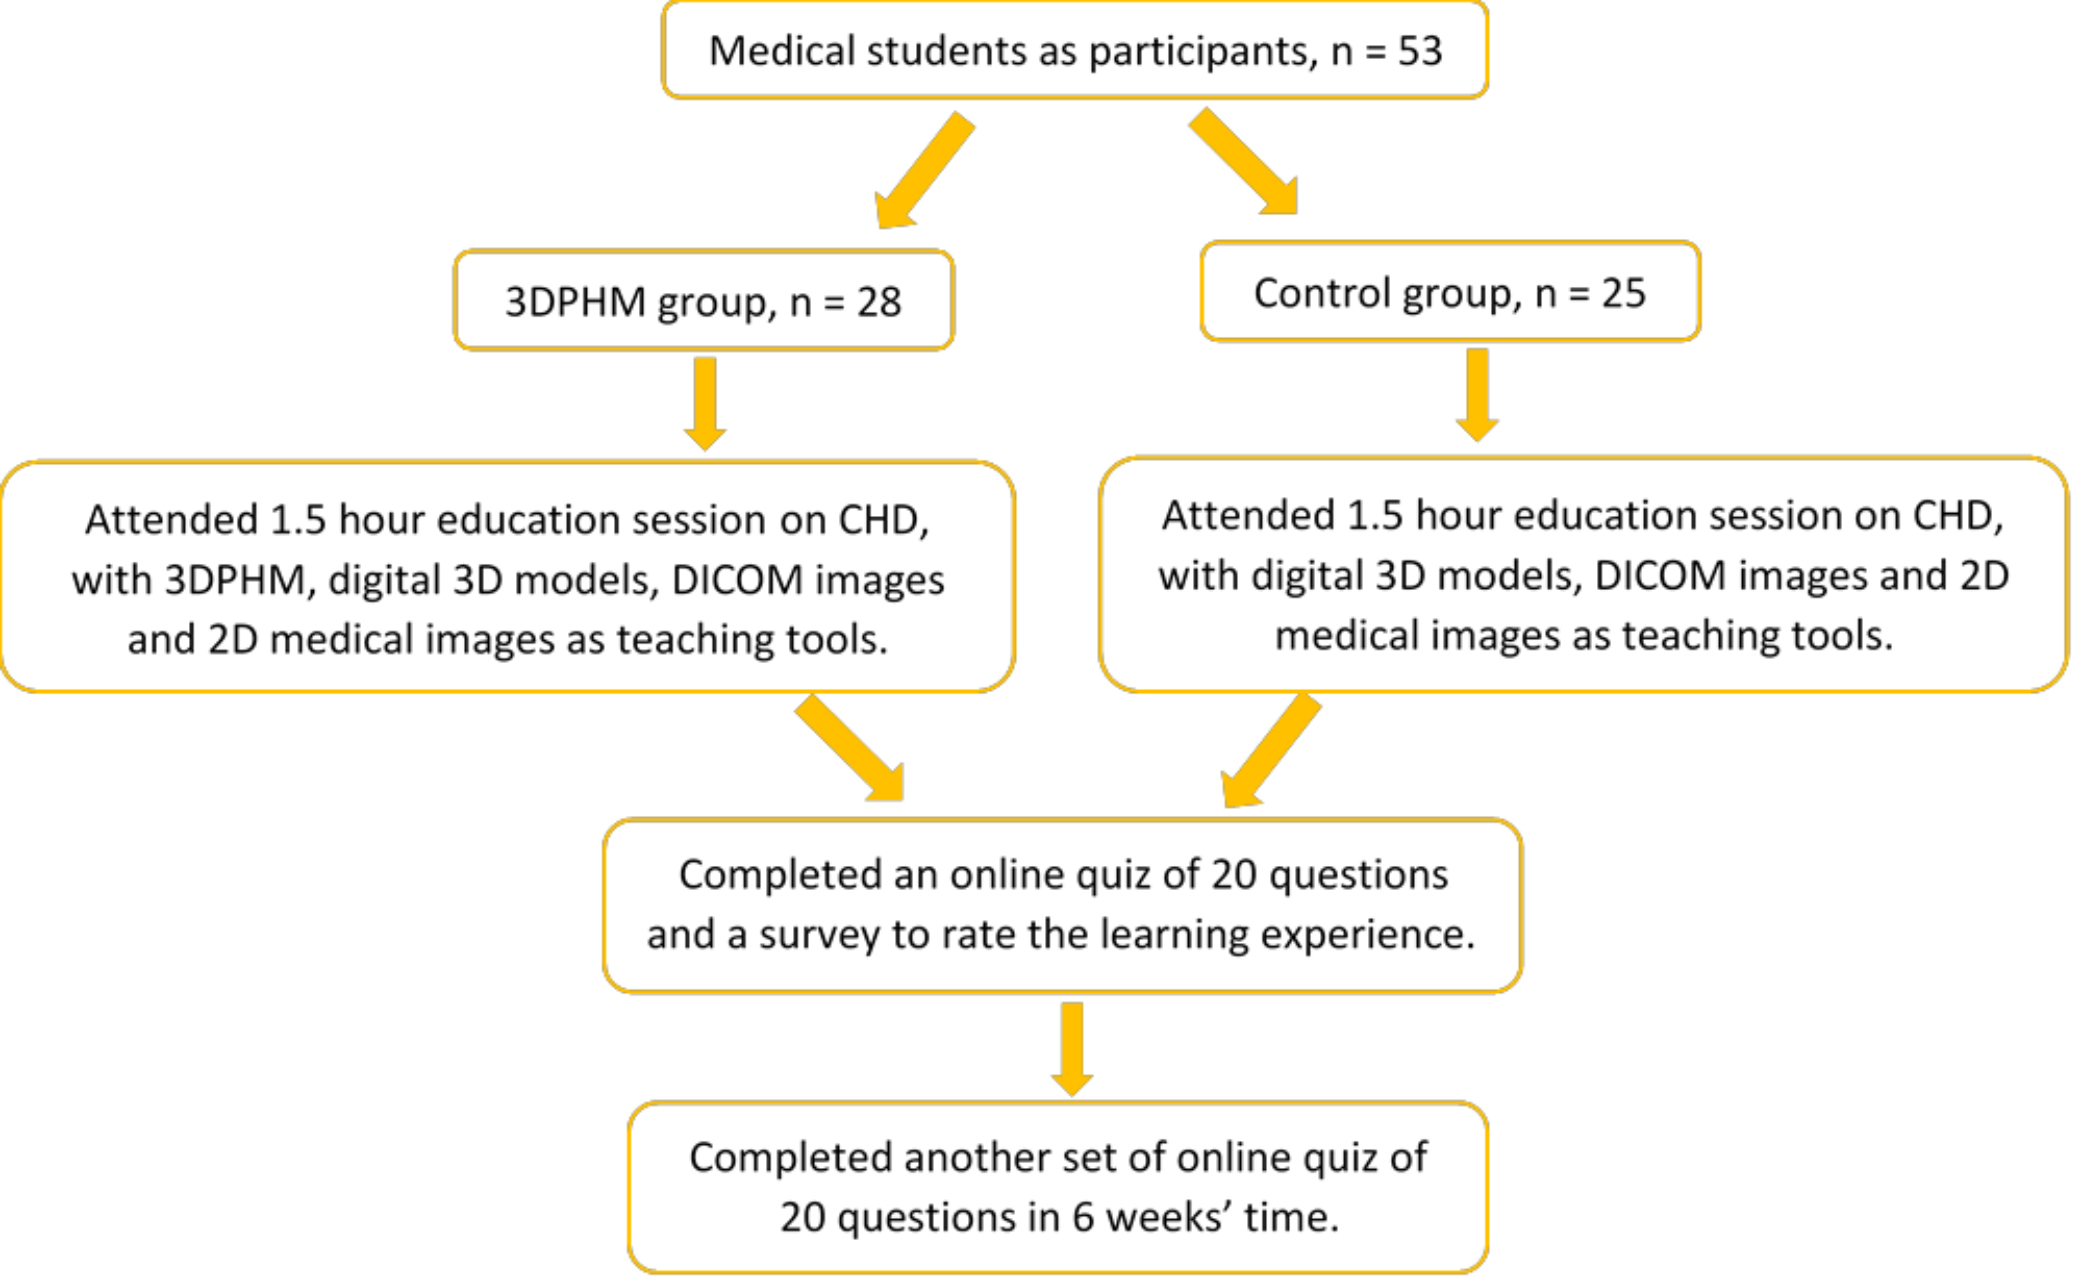

A prospective cohort study was conducted to compare the knowledge retention on the topic of CHD between the medical students who were exposed to conventional teaching approach versus those who were exposed to teaching approach with the use of 3DPHM. The study was approved by the Curtin University Human Research Ethics Committee. This research was advertised twice in first semester 2020 and first semester 2021 respectively in the Perth Campus, Curtin University. The participant recruitment was primarily limited to second and third year medical students in the year 2020, and only second year group in the year 2021, as these were the groups who were considered as novice in cardiac anatomy and pathology.

From both of the recruitments, a total of 53 medical students (5 in their 3rd year, and 48 in their 2nd year) voluntarily participated in the study. There were 5 education sessions on the topic of CHD carried out each year, with a duration of 1.5 hour for each of them. The participants were required to attend one of them based on their availability. A maximum of 9 students were allowed per session. To minimize potential bias, the participants were not informed if they were in the control or study group. There were 28 students who attended the education sessions with the use of 3D printed heart models (study group), and 25 students attended the education sessions without being presented with the 3D printed heart models (control group). All 53 medical students had previously been taught of CHD during their curriculum.

In order to assess the difference in knowledge gain and knowledge retention between the groups, the students completed two sets of quizzes which comprised of 20 questions relevant to CHD. The first set was completed immediately following the education session (immediate knowledge gain), while the second set was completed 6 weeks after the education session (knowledge retention). They also completed a survey to rate their learning experience. Appreciation gifts were given to the study participants at the completion of second quiz to prevent drop-outs.

Immediately after the education session, the participants were asked to complete a set of online quiz (Quiz 1) which comprised of 20 multiple choice and short-answer questions on CHD, with a time limit of 15 minutes. The participants were also asked to complete a survey to rate their learning experience based on a 5-point Likert scale. In 6 weeks’ time after the education session, the participants completed another online quiz (Quiz 2) of 20 questions, again with a time limit of 15 minutes. The score (out of 20) and the time taken for the participants to complete both of the quizzes were recorded. The process of the study is summarized in Fig. 4.

Fig. 4.

Fig. 4.A flow chart of the study process. 2D, two-dimensional; 3DPHM, three-dimensional printed heart model; CHD, congenital heart disease; DICOM, digital imaging and communications in medicine.